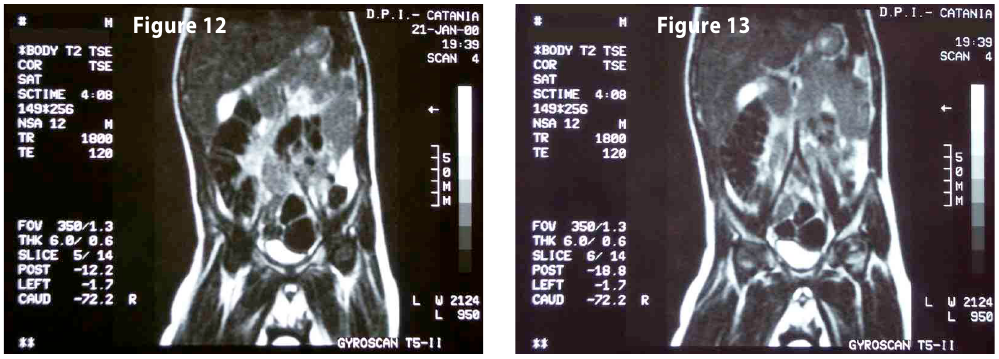

Complete objective response of neuroblastoma to biological treatment.

Figure12-13